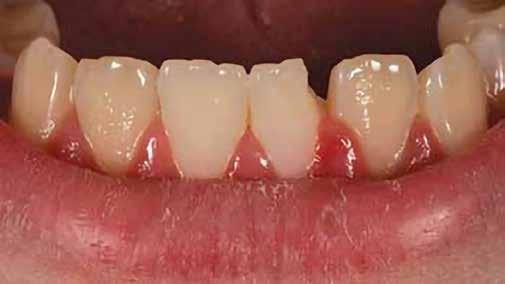

nak megfelelően – előkészítjük (orthofoszforsavval történő savazás, lemosás, szárítás és bond réteggel történő fedés). Ezzel egyidejűleg a ragasztásra kerülő héjak is előkészítésre kerülnek (hidrofolysavval történő savazás, lemosás, szárítás, szilanizálás, bond réteggel történő fedés, és végül az alkalmazni kívánt ragasztóanyag felvitele). Ezután a héjakat a fogak felszínén egyesével pozicionáljuk, majd néhány másodpercen keresztül polimerizációs lámpa segítségével megvilágítjuk. Ezt követően a kifolyó ragasztófelesleget eltávolítjuk, majd elvégezzük a restaurátumok végső polimerizálását. A héjak végleges rögzítését követően az esetlegesen visszamaradt ragasztómaradványok eltávolításra kerülnek, valamint ellenőrizzük az okklúzió és artikuláció közben létrejövő fogérintkezéseket. Az optimális esztétikai eredmény biztosítása érdekében kiemelt jelentősége van a papillák helyreállításának (rózsaszín esztétika). A modern fogorvoslás egyik kiemelt célja a fehér- és rózsaszín esztétika közti harmonikus egyensúly megteremtése. A papillák színe, nagysága és szimmetrikus megjelenése meghatározó szerepet tölt be a rózsaszín esztétika kialakításában. Az íny lefutása ugyancsak rendkívül jelentős mértékben befolyásolja a páciens fogazatának esztétikus megjelenését.

Manapság egyre gyakrabban találkozhatunk olyan páciensekkel, akik már a kezelések megkezdése előtt informálódnak a számukra elérhető kezelésekről, és ennek megfelelően jól definiált igényekkel érkeznek a rendelőnkbe. A páciensekkel történő megbeszélések során nagyon fontos, hogy részletesen felvilágosítsuk őket az általuk preferált kezelések előnyeiről és esetleges hátrányairól, valamint szintén

előnyös, ha egyéb terápiás alternatívákat is tudunk kínálni számukra.